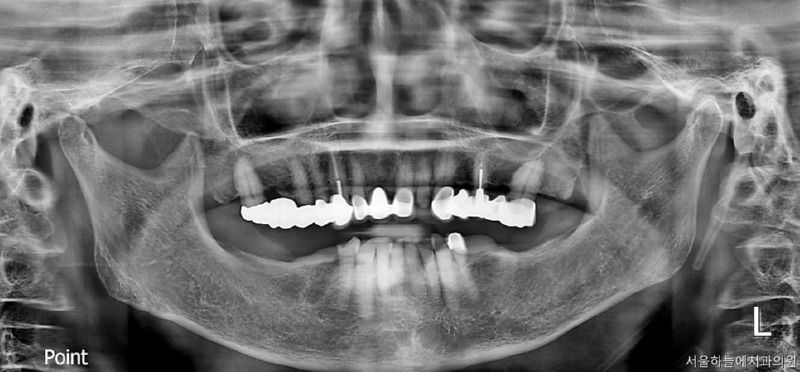

처음 내원 당시 엑스레이와 구강 상태를 보면

앞니는 파절되어 있었고

아래 어금니가 없는 기간이 길어

위 치아와 잇몸이 맞닿을 정도로 공간이 부족,

아래 앞니 역시 심하게 마모된 상태였습니다.